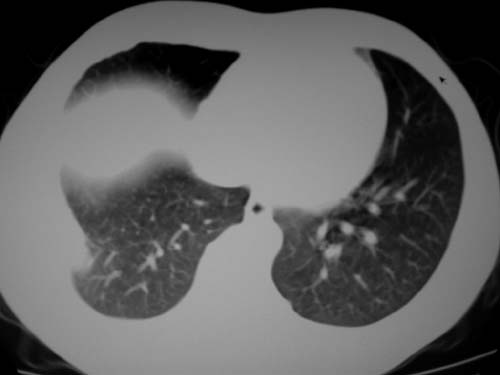

标题: CT19540: 31岁。自述结核性胸水治疗两个月后,在外院拍x线发 [打印本页]

标题: CT19540: 31岁。自述结核性胸水治疗两个月后,在外院拍x线发

右侧胸壁结节状软组织影伴相应肺叶内受侵,伴右侧胸腔积液。考虑:结核性可能大。

1、炎性包块;2、右侧少量胸膜积液。

1、炎性病变,结核可能;2、右侧少量胸膜积液。

病灶也是发生于结核球好发部位,支持结核

考虑结核性结节

多考虑包裹性胸腔识液。

右侧胸壁结节状软组织影伴相应肺叶内受侵,伴右侧胸腔积液,结合临床,首先考虑结核。

考虑结核性胸膜炎,胸膜肥厚,不除外胸膜间皮瘤可能,建议复查。

支持结核,胸膜间皮瘤不排除.

1)考虑右侧结核性胸膜结节。2)右侧胸膜增厚+包裹性胸腔积液。

结核性脓胸、肺内结核?